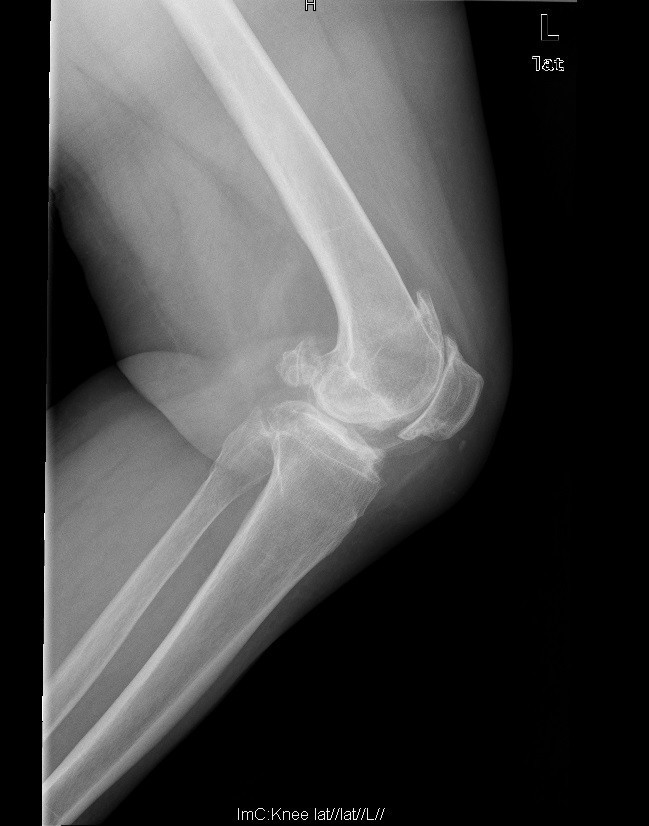

查体:步态跛行,双膝屈曲畸形,左膝外翻、右膝内翻畸形,双膝内外侧关节间隙及髌股关节间隙压痛明显,右侧重,右膝内翻:5°,右膝屈70°,伸-10°;左膝:屈曲:100°,伸:-5°,外翻:20°,双膝主被动屈伸活动时疼痛,双膝髌下摩擦音(+)。 辅助检查:右膝关节间隙狭窄,软骨下骨硬化,髌股关节间隙消失,左膝关节间隙狭窄,软骨下骨硬化,髌股关节间隙狭窄,双膝髌骨、股骨、胫骨周围大量骨赘形成,关节腔内均可见游离体。

诊断:1.双膝重度骨关节炎继发右膝屈曲内翻畸形,左膝屈曲外翻畸形(Krackow Ⅰ型)2.高血压病(3级 极高危) 治疗:积极行术前准备,待血压等稳定后于全麻下行右侧全膝关节置换术,术后常规治疗,并鼓励其锻炼。